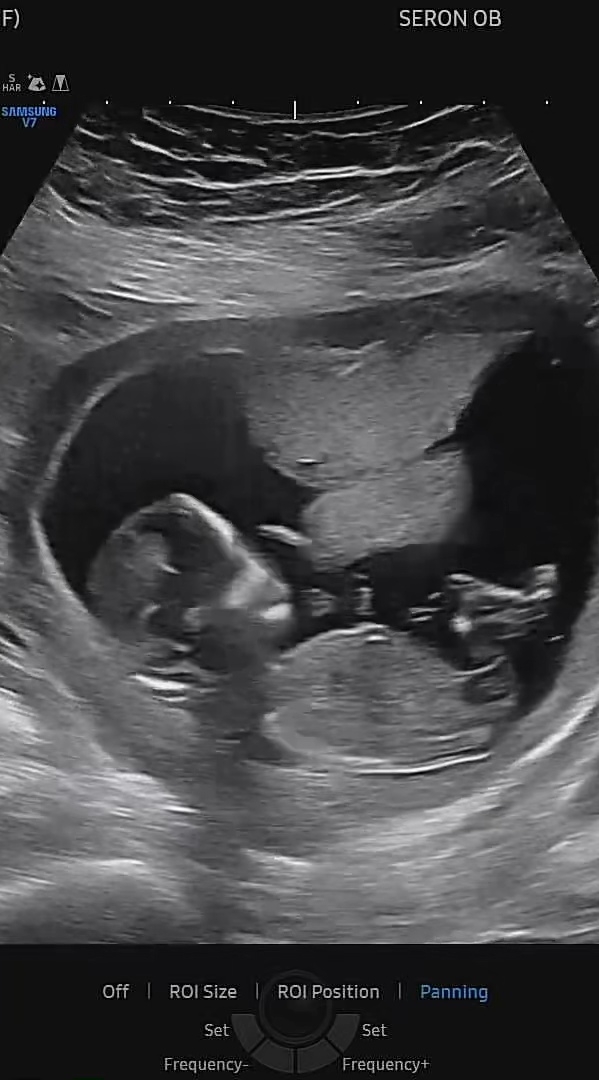

13주 5일차 성별 봐주셔요!!!

울애기 각도법으로 보려는데 다리 사이에 가려져 있는지 잘 안보이는데 어떻게 보이시나요??